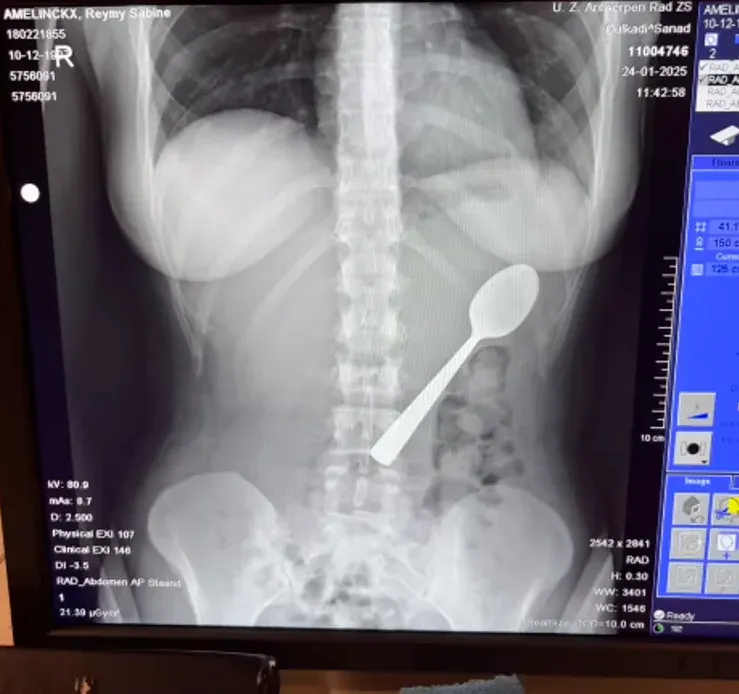

หลังเกิดเหตุ เธอไม่กล้าบอกแฟนหนุ่มในทันทีเพราะความอับอาย จนกระทั่งหลังมื้อค่ำ อาการเริ่มแย่ลงเรื่อยๆ เธอจึงถูกส่งตัวไปยังโรงพยาบาล แพทย์ถึงกับตะลึงเมื่อเห็นภาพเอกซเรย์ เพราะช้อนมีขนาดใหญ่เกินกว่าจะขับถ่ายออกมาเองตามธรรมชาติได้ เธอต้องรอคิวทำส่องกล้องนานถึง 2 วัน ซึ่งในช่วงเวลานั้นเธอยังรู้สึกได้ว่าช้อนเคลื่อนที่ไปมาอยู่แถวซี่โครง สร้างความเจ็บปวดและทรมานเป็นอย่างมาก

โชคดีที่ทีมแพทย์สามารถนำช้อนออกมาได้สำเร็จผ่านการวางยาสลบเฉพาะจุด แม้กระบวนการจะยากลำบากเพราะขนาดของช้อนที่ต้องปรับองศาอย่างระมัดระวังจนทำให้มีเลือดออกในกระเพาะอาหารเล็กน้อย และมีอาการเจ็บคอตามมาอยู่พักใหญ่ แต่ในที่สุดเธอก็หายเป็นปกติโดยไม่มีความเสียหายถาวรต่อร่างกาย